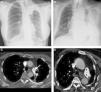

A) Radiografía de tórax posteroanterior de una paciente de 52 años (paciente X de aquí en adelante) con antecedente de carcinoma broncogénico tratado con quimioterapia y radioterapia 7 años antes, en la que se observa una atelectasia completa del LSI. B) Radiografía de tórax posteroanterior de un paciente de 85 años (paciente Y de aquí en adelante) en la que se observa una extensa paquipleuritis izquierda calcificada y una importante pérdida de volumen del hemitórax ipsilateral. C) Imagen axial de TC de la paciente X en la que se identifica un defecto de repleción aparente en la arteria pulmonar principal izquierda (flecha), que se interpretó erróneamente como un TEP. D) Imagen axial de TC del paciente Y en la que se observa otro defecto de repleción aparente en la arteria pulmonar principal izquierda (flechas), que también se interpretó equivocadamente como un TEP.

Presentamos 2 casos diagnosticados erróneamente de TEP agudo en urgencias de nuestro hospital. Los 2 pacientes consultaron por dolor torácico y disnea, y ambos presentaban una elevación del dímero-D e importantes alteraciones estructurales del hemitórax izquierdo: en un caso secundarias a cambios posradioterapia por un carcinoma broncogénico en remisión clínica (fig. 1A), y en el otro secundarias a una paquipleuritis tuberculosa calcificada de larga evolución (fig. 1B). La distorsión anatómica de las estructuras torácicas en general (pérdida de volumen del hemitórax izquierdo, desplazamiento del mediastino), y de las arterias pulmonares en particular (tracción y acodamiento de las arterias pulmonares), condicionó la formación de artefactos relacionados con un flujo turbulento de sangre (y del contraste intravenoso) en las arterias pulmonares del hemitórax izquierdo, visualizándose en la APTC como defectos de repleción aparentes en el interior las arterias pulmonares (figs. 1C y D). La adquisición de fases de TC de tórax más tardías (en las que existe una mayor dilución del contraste intravenoso) permitió descartar los defectos de repleción en las arterias pulmonares y confirmar la naturaleza artefactual de dichos defectos. Ninguno de los 2 casos presentaba otros defectos de repleción en la circulación pulmonar ni signos de sobrecarga de cavidades cardiacas derechas o de trombosis venosa profunda. Estos 2 ejemplos reflejan la importancia de comprender la fisiopatología y las implicaciones vasculares y hemodinámicas de las alteraciones estructurales del tórax, especialmente de las arterias pulmonares.